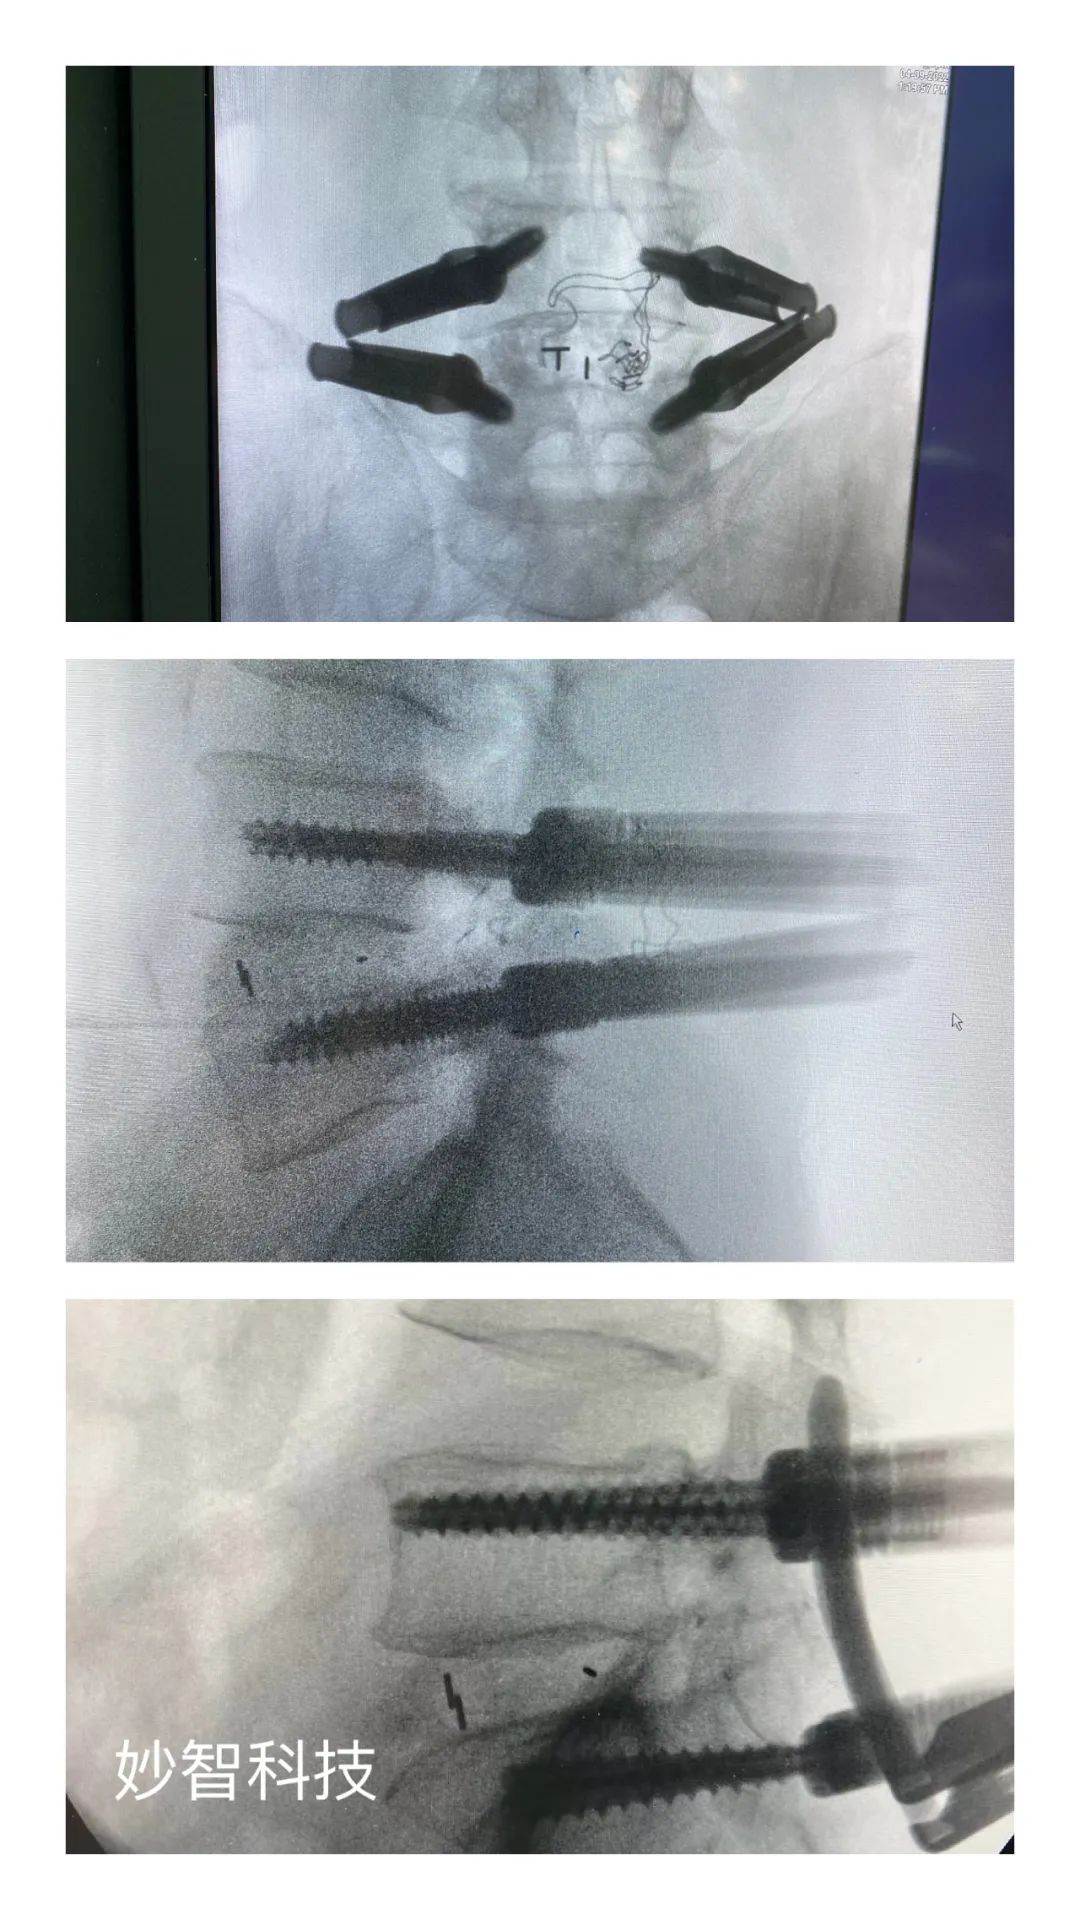

妙智科技研发的骨科机器人在临床中试验

由于新型医疗器械一般研究周期较长,目前,妙智科技研发的骨科机器人仍在临床试验阶段。截至 2022 年底,妙智科技已经完成了近 50 例临床病例,预计今年计划将完成取证并开始售卖。

其中,MVROT 脊柱外科手术导航系统(手术机器人)作为妙智科技在研的一种智能手术治疗产品,主要用于脊柱外科开放或经皮手术中,通过7自由度,ForceFeedBack机械臂来辅助临床医生完成手术器械或植入物的定位,支持术前CT-术中2D C Arm影像配准,系統空间精度1.5mm,力学测量精度0.25N,工作范围 40cm X 40cm X 40 cm,为市场领先指标。该产品目标是使复杂的手术简单化、精准化、可视化,安全度高、易操作,医生学习曲线短,提高手术效率,大幅降低医生和患者X线辐射量,大幅减少病人看病成本。